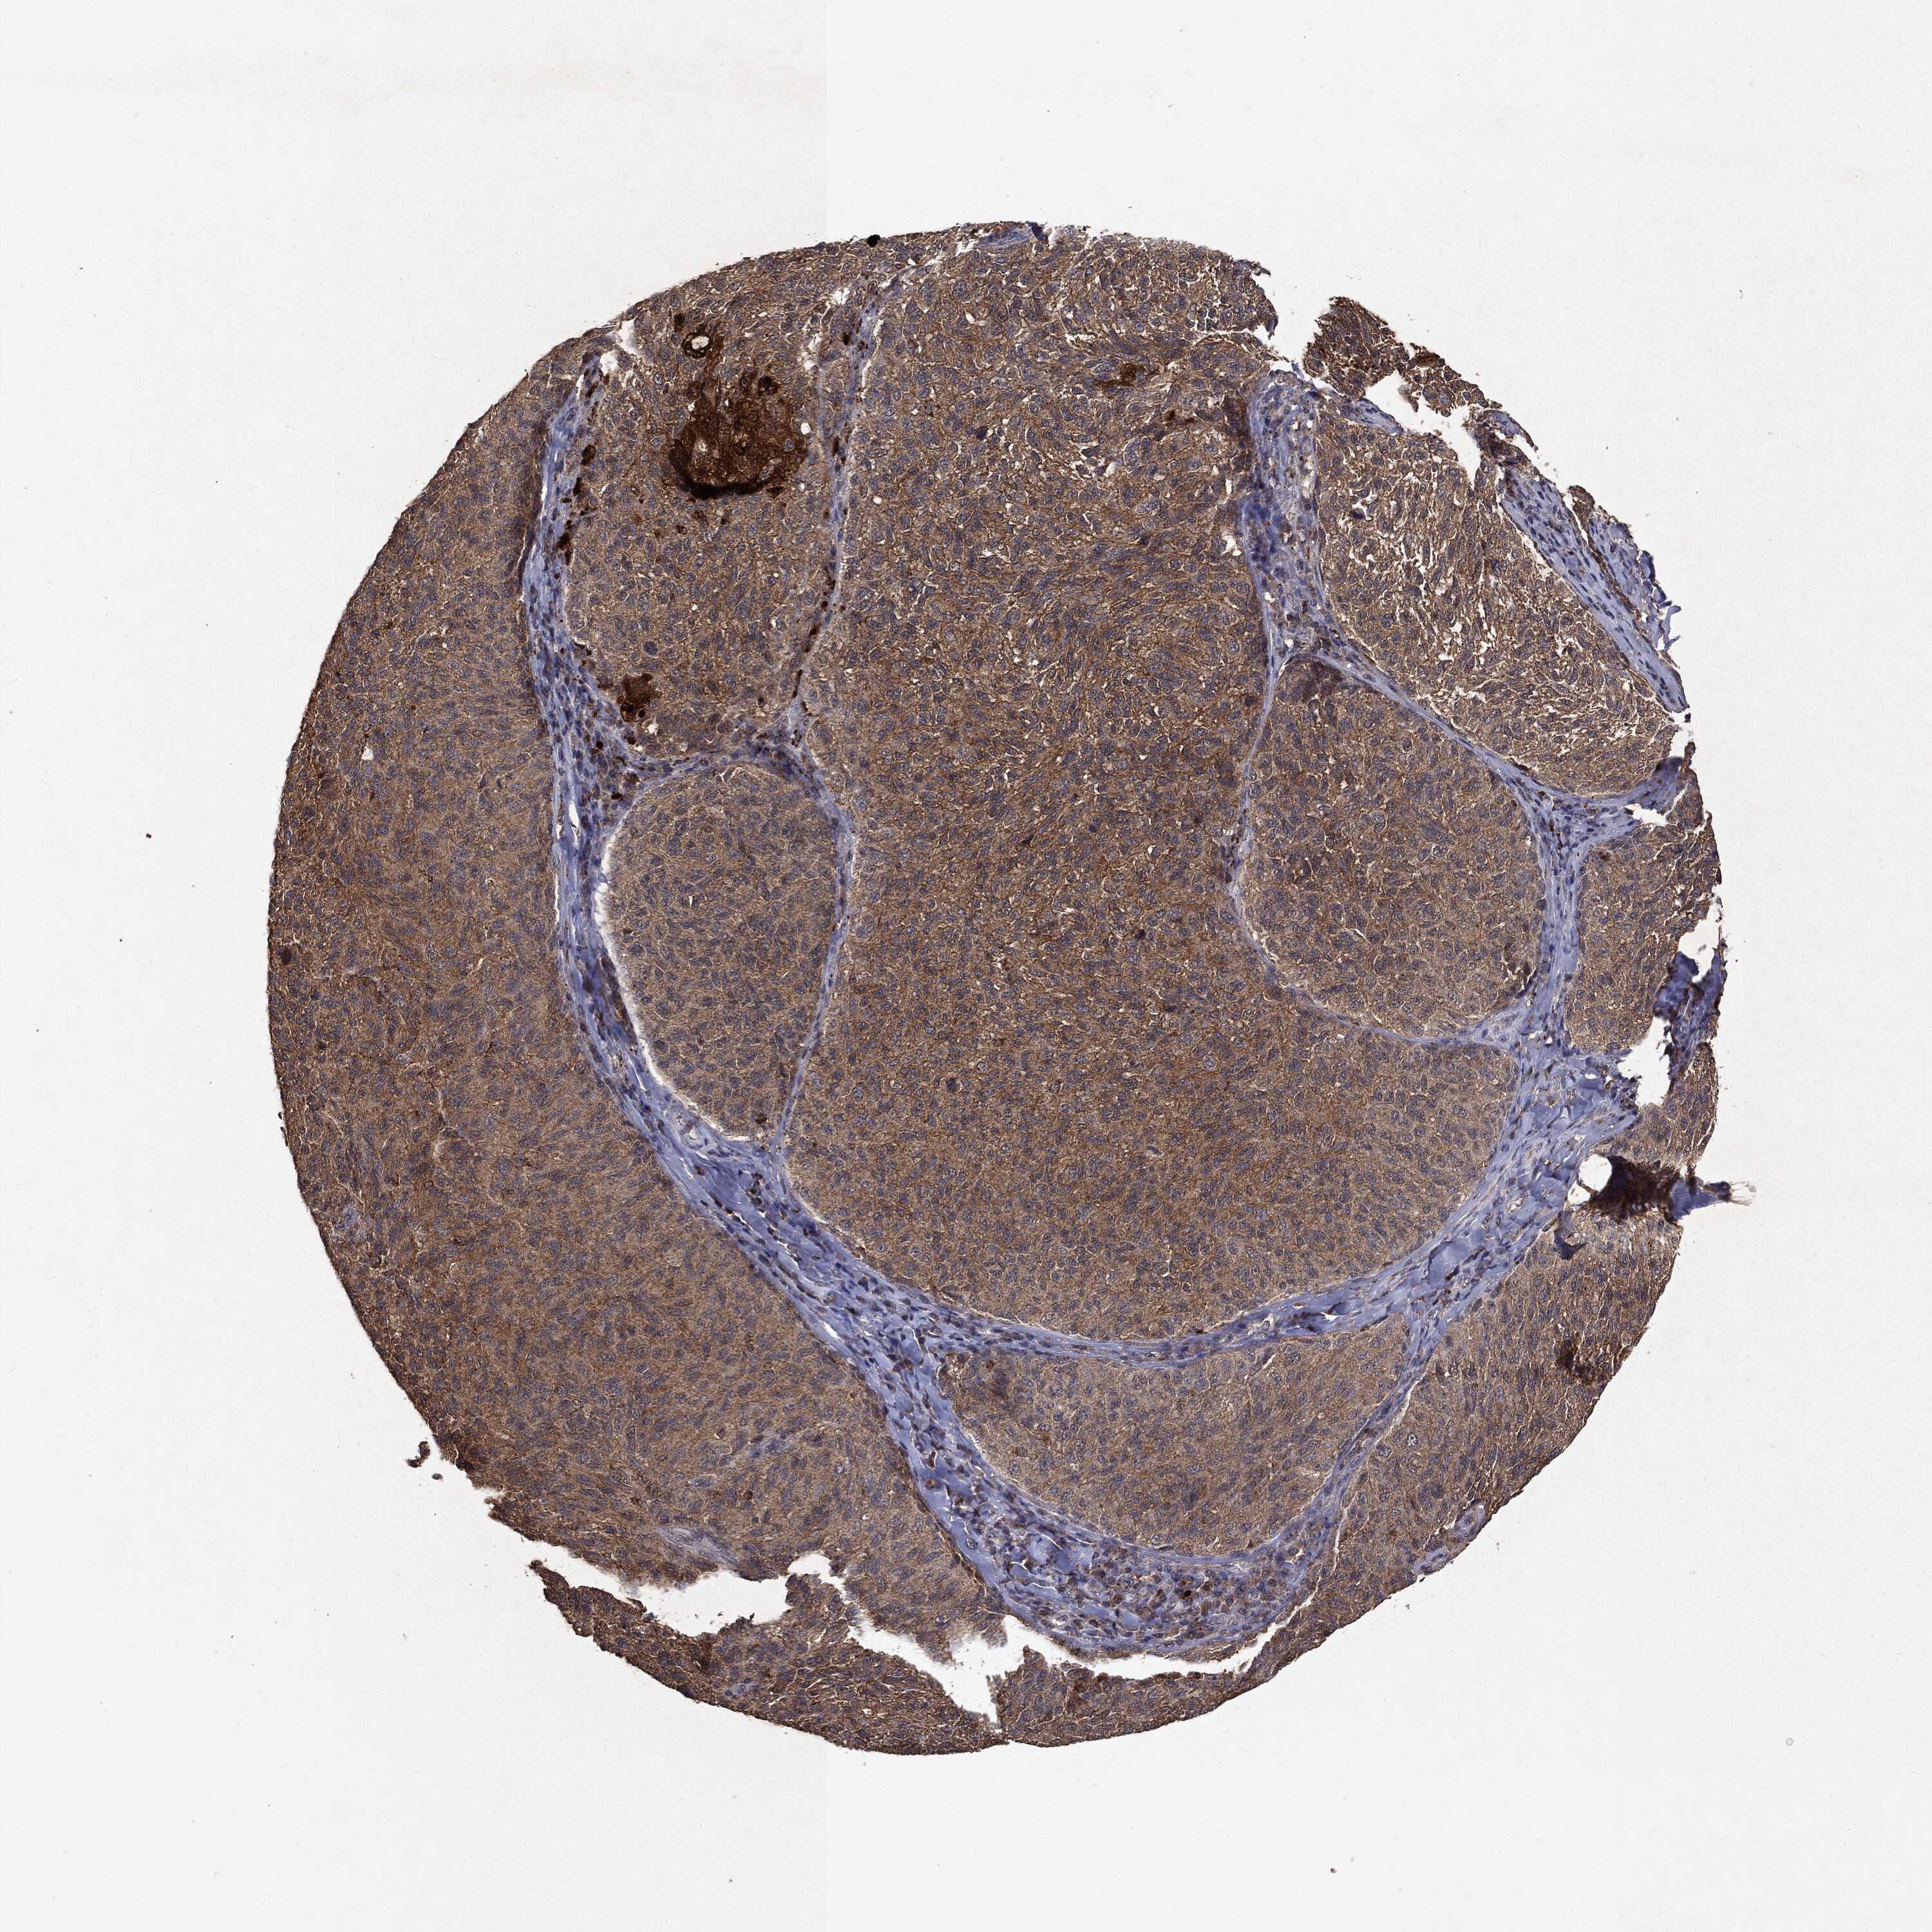

MELANOMA - Protein expressioni

A mouse-over function shows sample information and annotation data. Click on an image to view it in a full screen mode. Samples can be filtered based on level of antibody staining by selecting one or several of the following categories: high, medium, low and not detected. The assay and annotation is described here.

Note that samples used for immunohistochemistry by the Human Protein Atlas do not correspond to samples in the TCGA dataset.

Antibody stainingi

Antibody staining in the annotated cell types in the current human tissue is reported as not detected, low, medium, or high, based on conventional immunohistochemistry profiling in selected tissues. This score is based on the combination of the staining intensity and fraction of stained cells.

Each image is clickable and will lead to virtual microscopy that enables deeper exploration of all samples and also displays staining intensity scores, fraction scores and subcellular localization as well as patient and tissue information for each sample.

CAB069425

CAB080053

CAB080065

CAB080070

CAB080081

CAB080095

CAB080097

Staining

High

Medium

Low

Not detected

Intensity

Strong

Moderate

Weak

Negative

Quantity

>75%

75%-25%

<25%

None

Location

Nuclear

Cytoplasmic/membranous

Cytoplasmic/membranous,nuclear

Malignant melanoma, NOS

Malignant melanoma, Metastatic site